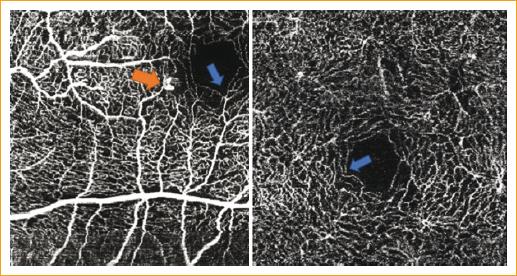

El plexo vascular más afectado fue el profundo, en un 94%. En el 35% de los pacientes se logró visualizar vasos en ángulo recto (Fig. 3). Las características morfológicas que observamos en los vasos afectados fueron: un engrosamiento con dilataciones focales y, solo en el 33%, lesiones aneurismáticas con morfología (Fig. 3).

Figura 3 A la izquierda, angiografía por tomografía de coherencia óptica con lesión vascular temporal a la fóvea. Se observa lesión aneurismática en el plexo superficial (flecha naranja). Ambas imágenes con vasos en ángulo recto (flecha azul).